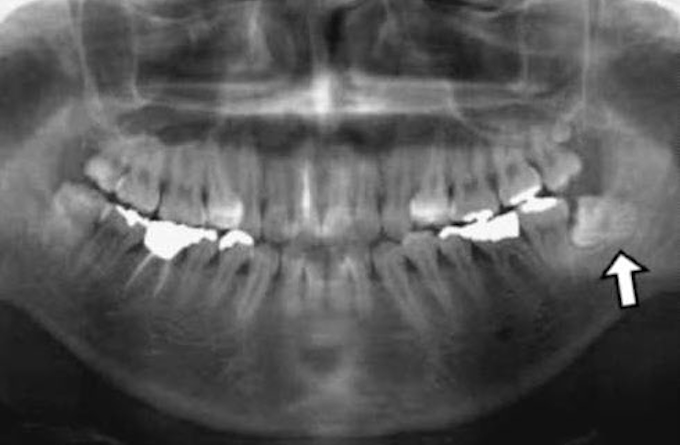

右下 水平埋伏智歯 抜歯手順 画像 14 06 28 スタッフブログ 三好デンタルオフィス

親知らずの抜歯はctでリスクを正しく判断 抜歯で麻痺の後遺症も 歯医者 歯科医院の選び方が変わる デンタルマイクロスコープclinic

神経に当たっていた親知らずを浮き上がらせて治療 福岡市早良区飯倉で歯周病を予防する歯医者 もろとみ歯科

神経に触れている親知らず ネット予約可 静岡市の歯医者は小嶋デンタルクリニック